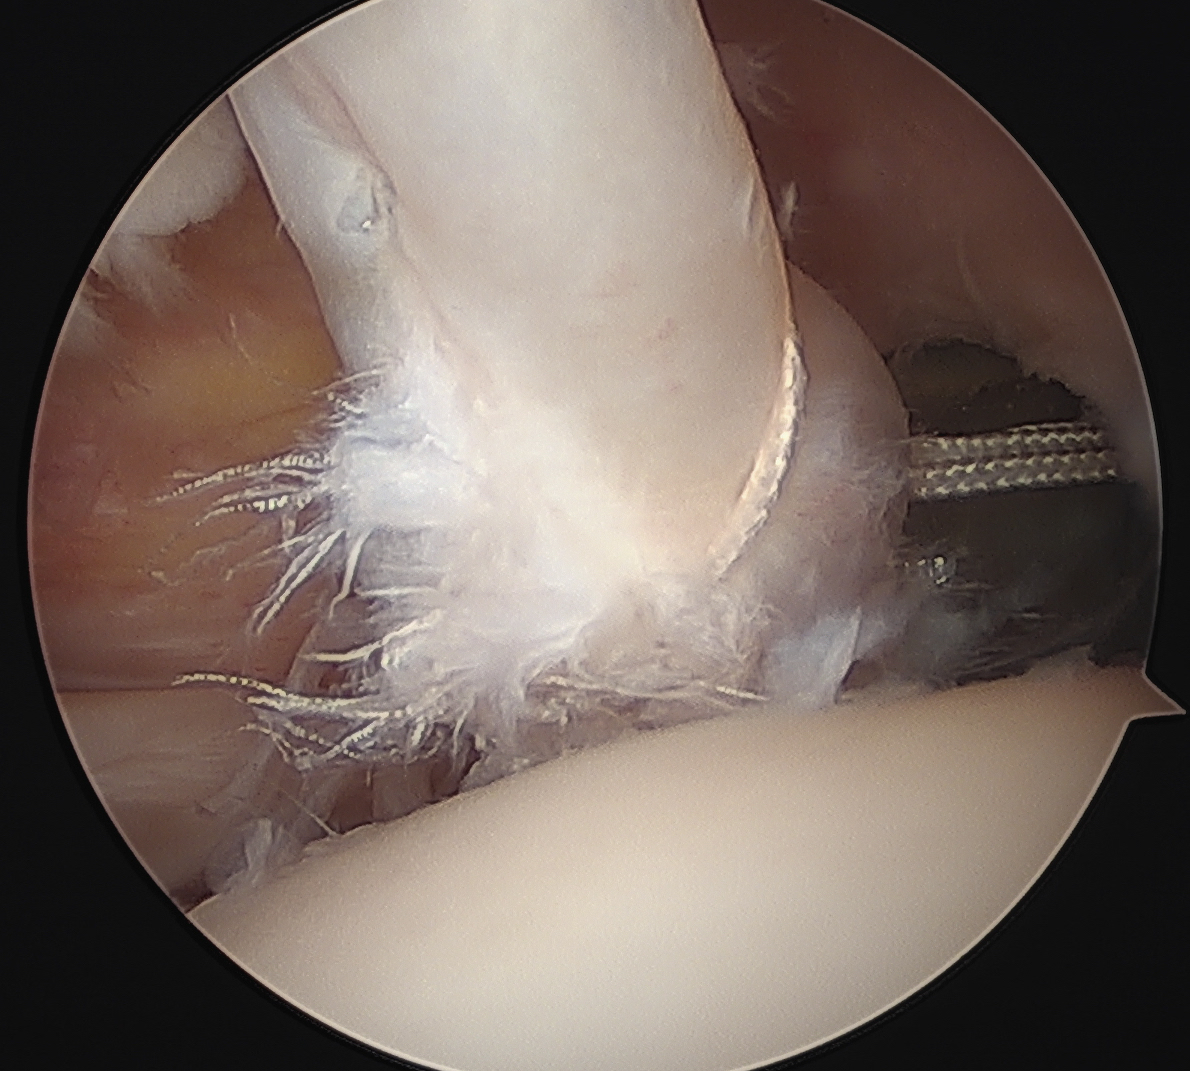

Medially dislocated biceps tendon with upper border subscapularis tear

Full thickness tear of subscapularis off insertion revealed with grasper